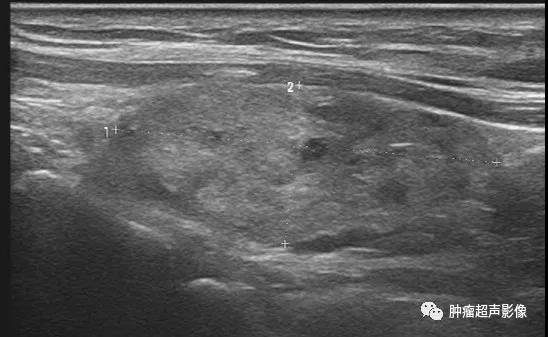

异位甲状腺(迷走甲状腺):正常甲状腺位置未见甲状腺回声,颌下见甲状腺样组织回声,回声不均,血流丰富,类似甲亢表现(推测功能不足,代偿性)